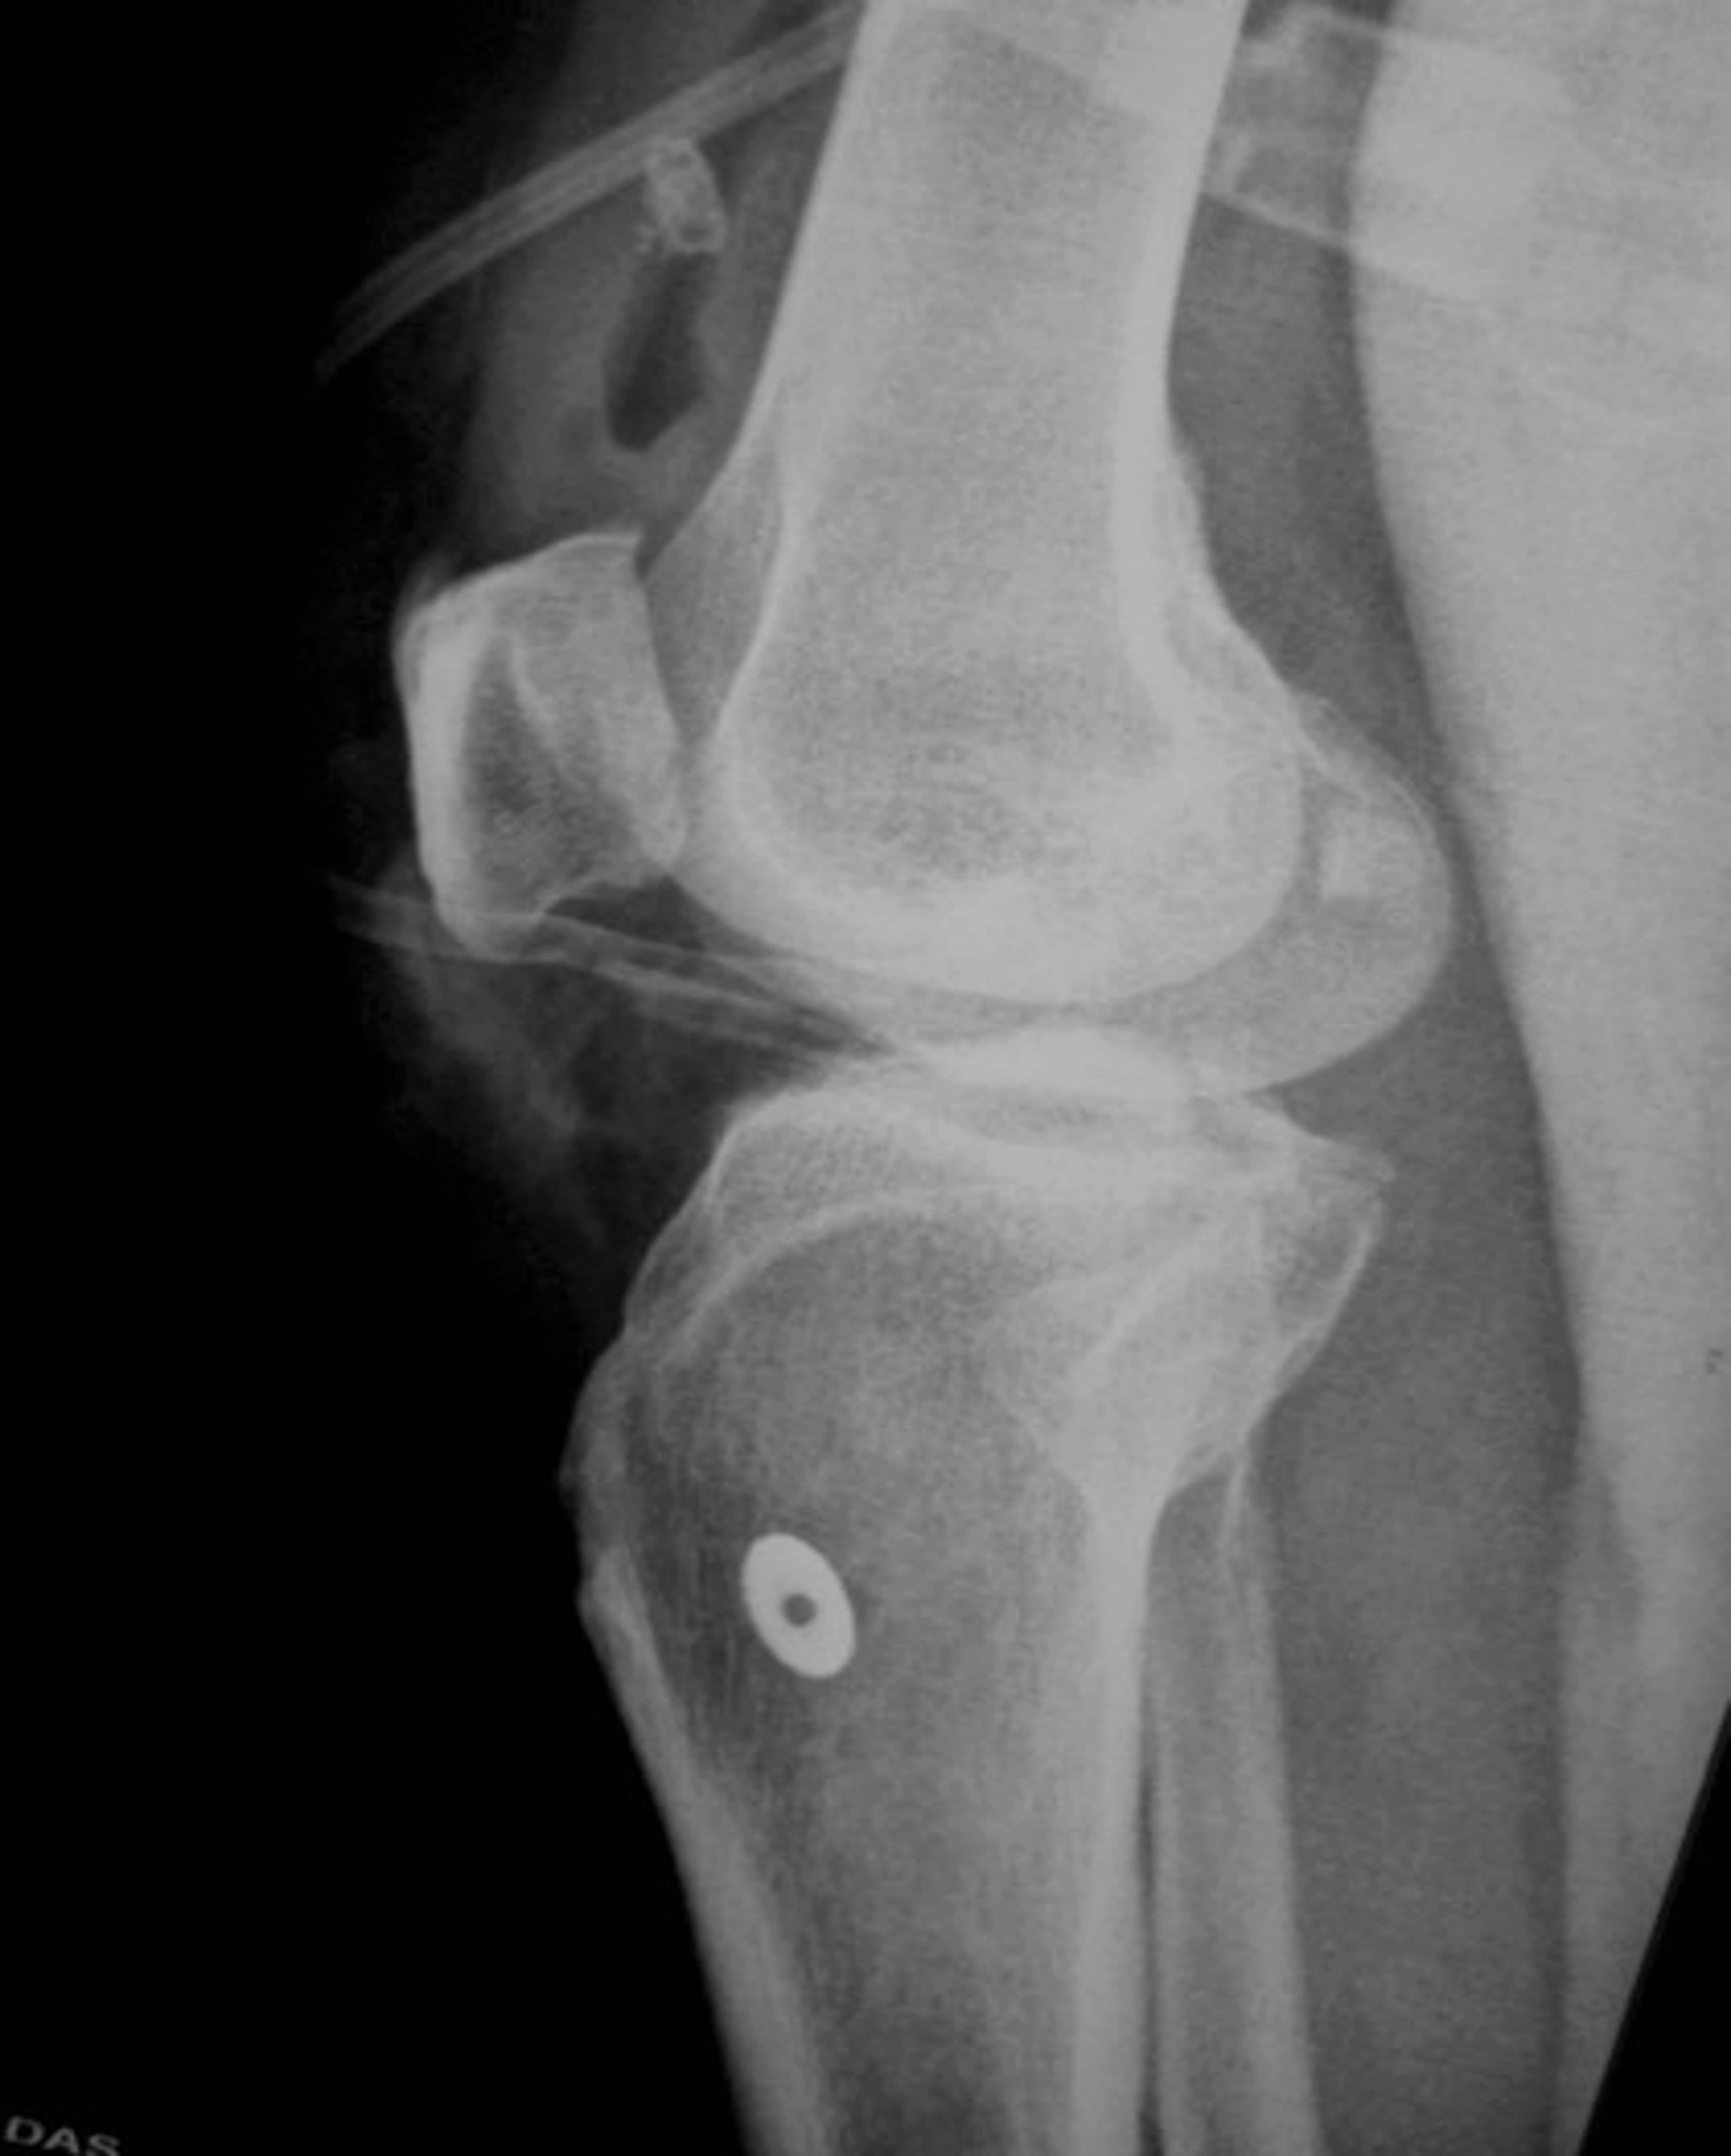

Case 1

Case 1 pre op xrays and post op xrays